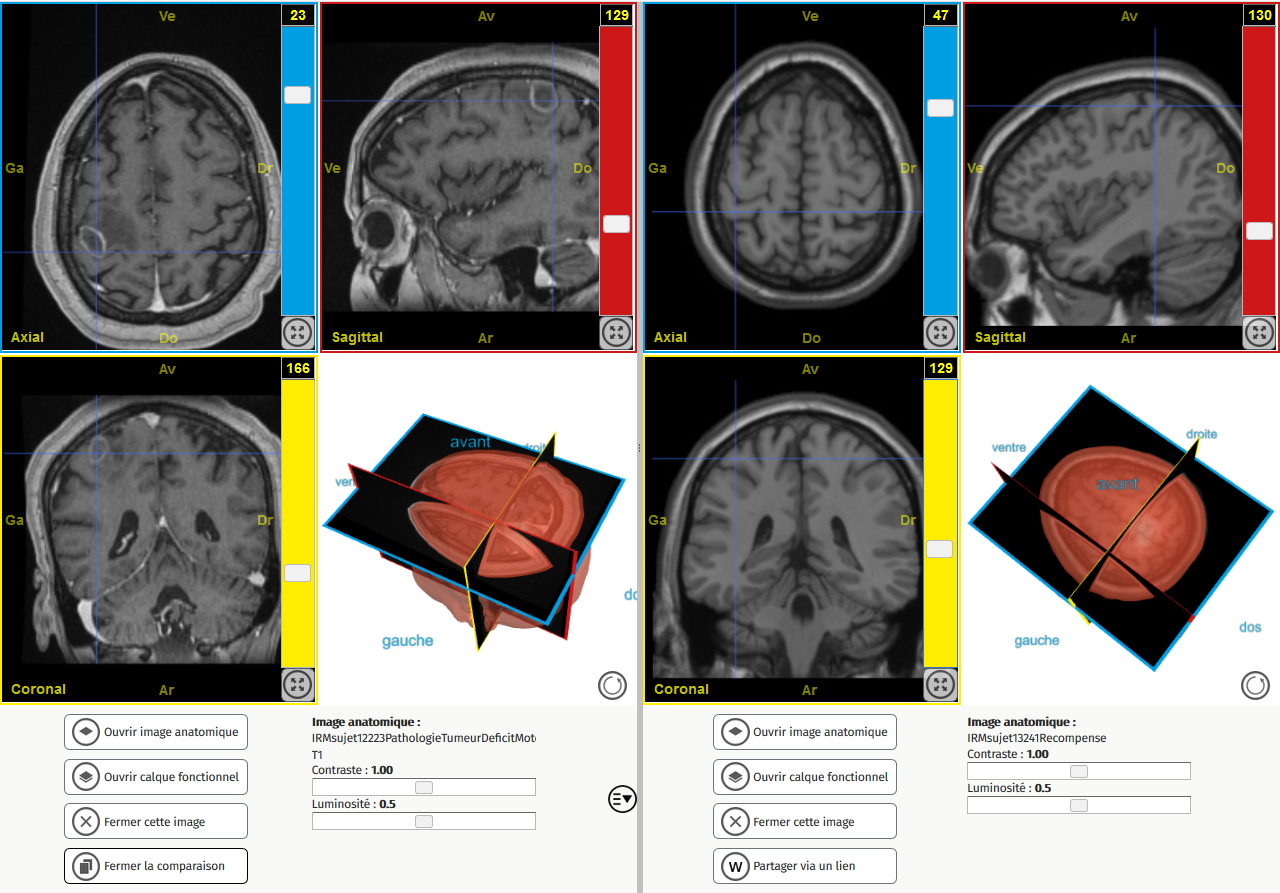

Comparaison deficit moteur droit T1

Image dans sa taille originale :

753 ko